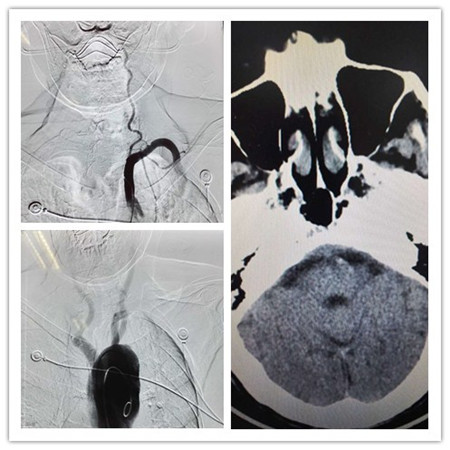

2月11日晚9点半,94岁的老太太朱某因突发意识不清2小时被家人送到西安交大二附院。老人既往有房颤病史,一天前才从海南旅游归来。入院时呈浅昏迷,四肢瘫痪,压眶刺激未见肢体活动。急诊科、CT室立即启动院内绿色通道,20分钟内完成CT扫描未见出血,急请神经内科会诊,考虑基底动脉血栓,病情十分危重,在神内张桂莲主任指导下,10分钟内静脉给予rtPA溶栓治疗。并立即行脑血管造影手术,同时做好取栓手术准备。但因患者年龄过大,血管条件非常差,全程主要动脉从腹主动脉、胸主动脉均高度迂曲,主动脉弓也扭转变形,王虎清、孙宏两位副教授经45分钟完成了部分主要血管造影,张桂莲教授亲自上台,在两位医生的配合下,最终采用交换、同轴套管等多种神经介入技术,经过1小时多的奋战终于将微导管送到目标罪犯血管附近,检查发现基底动脉中段以远血流明显减少,隐约可见中远段基底动脉明显扩张,考虑基底动脉可能原本存在血管夹层,这次发病可能是在基底动脉夹层的基础上,心脏栓子脱落发生基底动脉栓塞。在病变血管段,虽然微导丝难以进入基底动脉,但此时发现患者临床症状已明显好转,意识转清醒,可回答简单问题,四肢可抬离床面,握手有力,医生果断停止手术。次日晨患者病情完全恢复至正常,复查头颅CT未见出血。